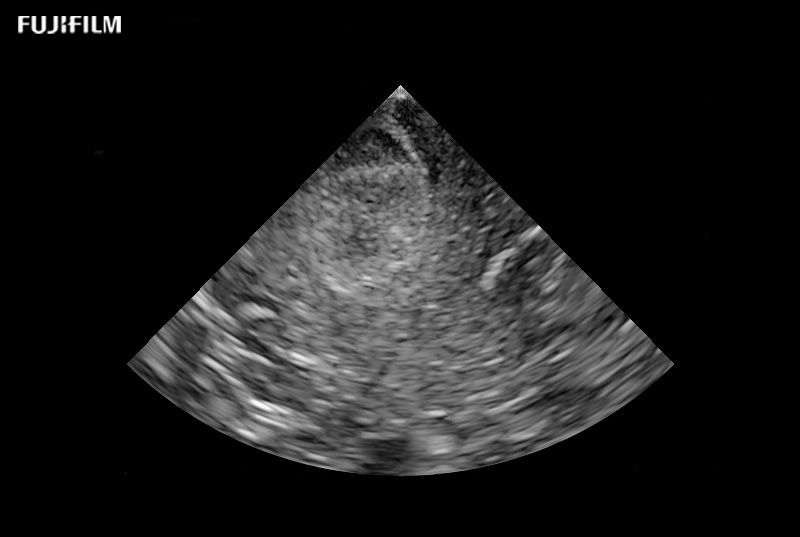

eFocusing is a transmission and reception technology to achieve clarity of imaging from near to far field. Reduced focus dependency and patient dependency.